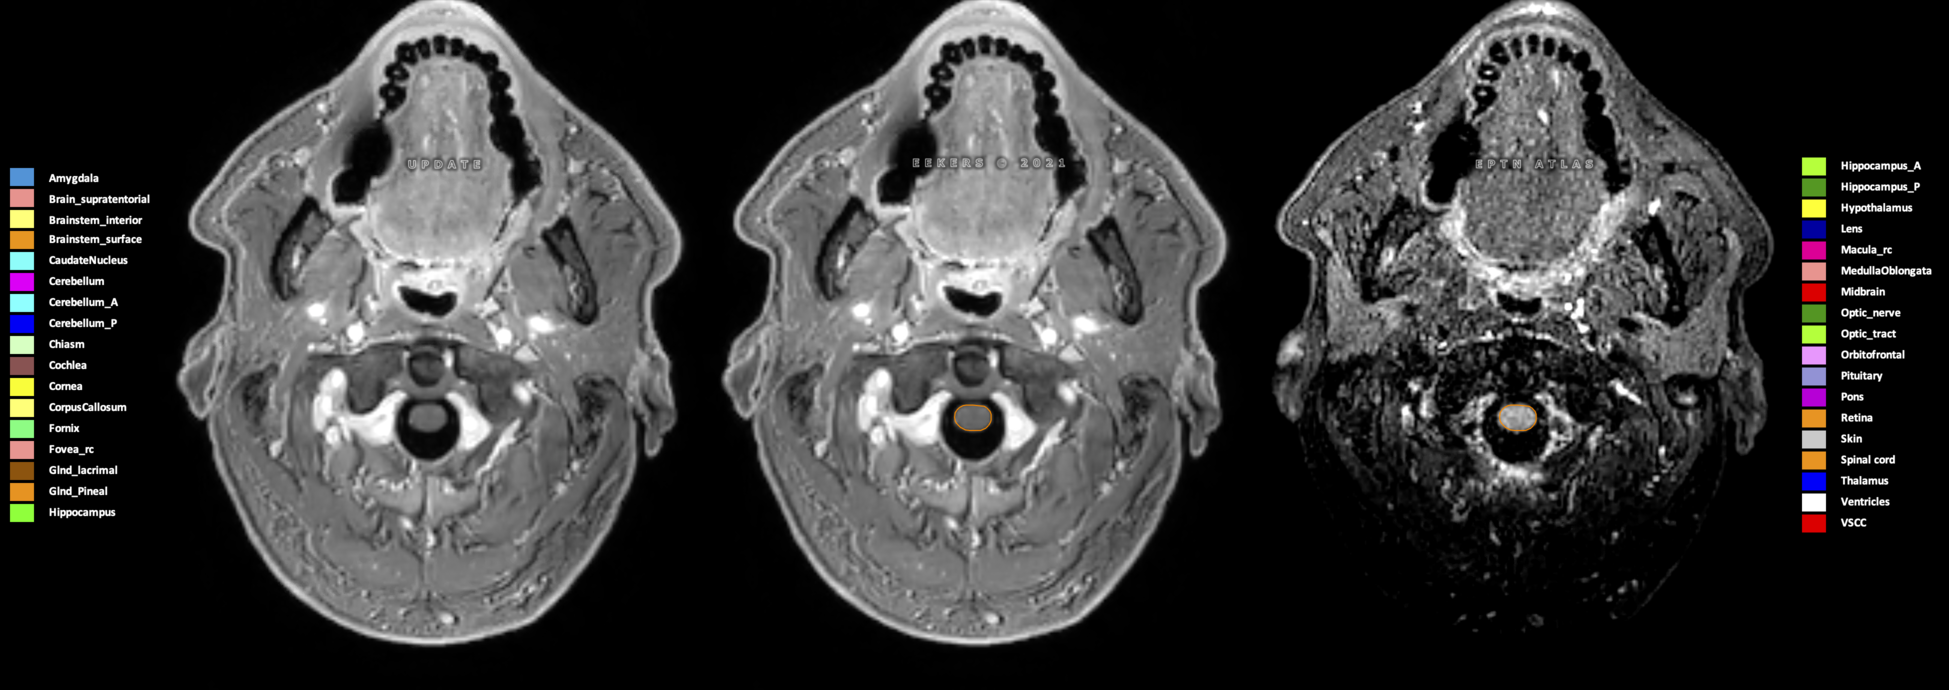

Eekers et al. have published an international neurological atlas for contouring of organs at risk in consensus with the European Particle Therapy Network (EPTN) in 2018 and an update in 2021. The purpose of this consensus atlas is to decrease inter- and intra-observer variability in delineating OARs relevant for neuro-oncology.

Included are all OARs known to be relevant for radiation-induced toxicity in neuro-oncology: brain, brainstem (midbrain, pons, medulla oblongata), chiasm, cerebellum (anterior & posterior), cochlea, cornea, hippocampus (anterior & posterior), hypothalamus, lens, lacrimal gland, optic nerve, pituitary, skin, and vestibular & semicircular canals. To further facilitate research on cognition, vision and radiological changes after irradiation of the brain, potential clinically-relevant OARs are included: amygdala, caudate nucleus, cerebellum (anterior & posterior), corpus callosum, fornix, macula, optic tract, orbitofrontal cortex, periventricular space (PVS), pineal gland, and thalamus.

Three-dimensional delineation of the 25 consensus OARs for neuro-oncology are shown on CT (WW/WL 120/40, 3000/600), 3T MR images, (T1Gd, T2FLAIR 1mm) and 7T MR (MP2RAGE 0.7 mm). All are presented in transversal, sagittal and coronal view.